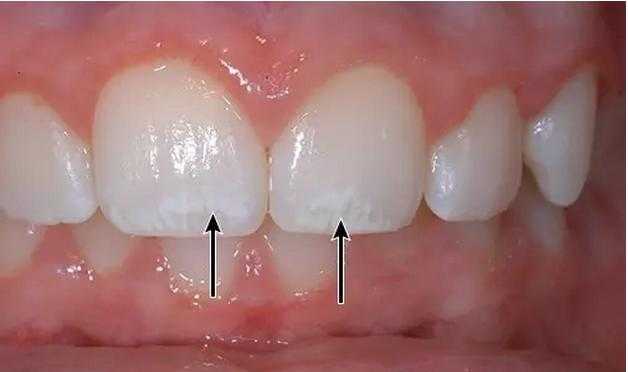

门牙缝大“漏财”还毁颜值,牙医教你2招关缝纳财!

我的 5mm 大牙缝 就是这样合拢的!

牙缝太大怎么办?是牙齿矫正?还是贴面呢?